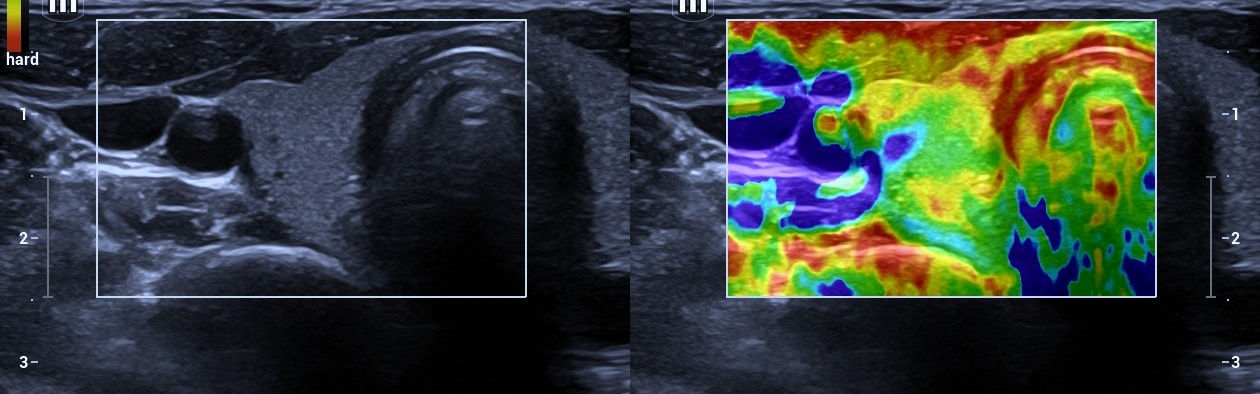

• Thyroid disorders (hypothyroidism, hyperthyroidism, nodules)

• Precise hormonal testing & diagnostics

• Modern technology, minimal wait time